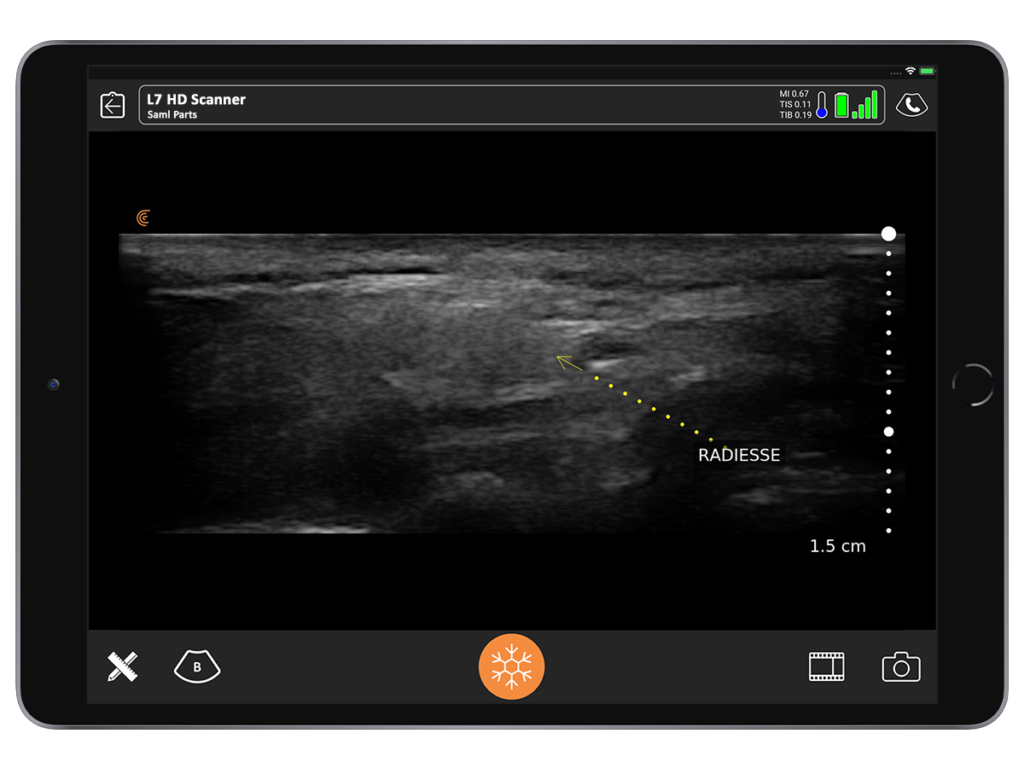

Sometimes I encounter deep nodules that patients say they can feel, but I can barely feel. A nodule may been caused by an injection with calcium hydroxyapatite that was given a year ago or longer. With ultrasound, we can see the nodule and perform a direct triamcinolone injection to ensure it goes directly into the little nodule.